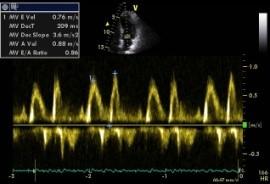

Echokardiografie: LEVÁ KOMORA bez dilatace a hypertrofie, s normální systolickou funkcí a regionální kinetikou kromě D shape, EF LK 55-60%. Diastolická funkce: porucha relaxace LK. PRAVÁ KOMORA FAC PK 18%, TAPSE 13 mm, Vt 9 cm/s, dilatace a hypertrofie PK, těžká prekapilární PH, odhadovaný PASP 90 mmHg, MPAP 55 mmHg, malý perikardiální výpotek

Echokardiografie: LEVÁ KOMORA bez dilatace a hypertrofie, s normální systolickou funkcí a regionální kinetikou kromě D shape, EF LK 55-60%. Diastolická funkce: porucha relaxace LK. PRAVÁ KOMORA FAC PK 19%, TAPSE 17 mm, Vt 9 cm/s, dilatace a hypertrofie PK, těžká prekapilární PH, odhadovaný PASP 130

mmHg, perikardiální výpotek